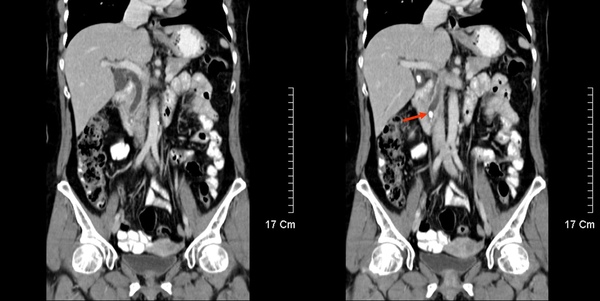

這位患者同時存在膽囊結石及腎臟結石。(紅色箭頭及黃色箭頭)